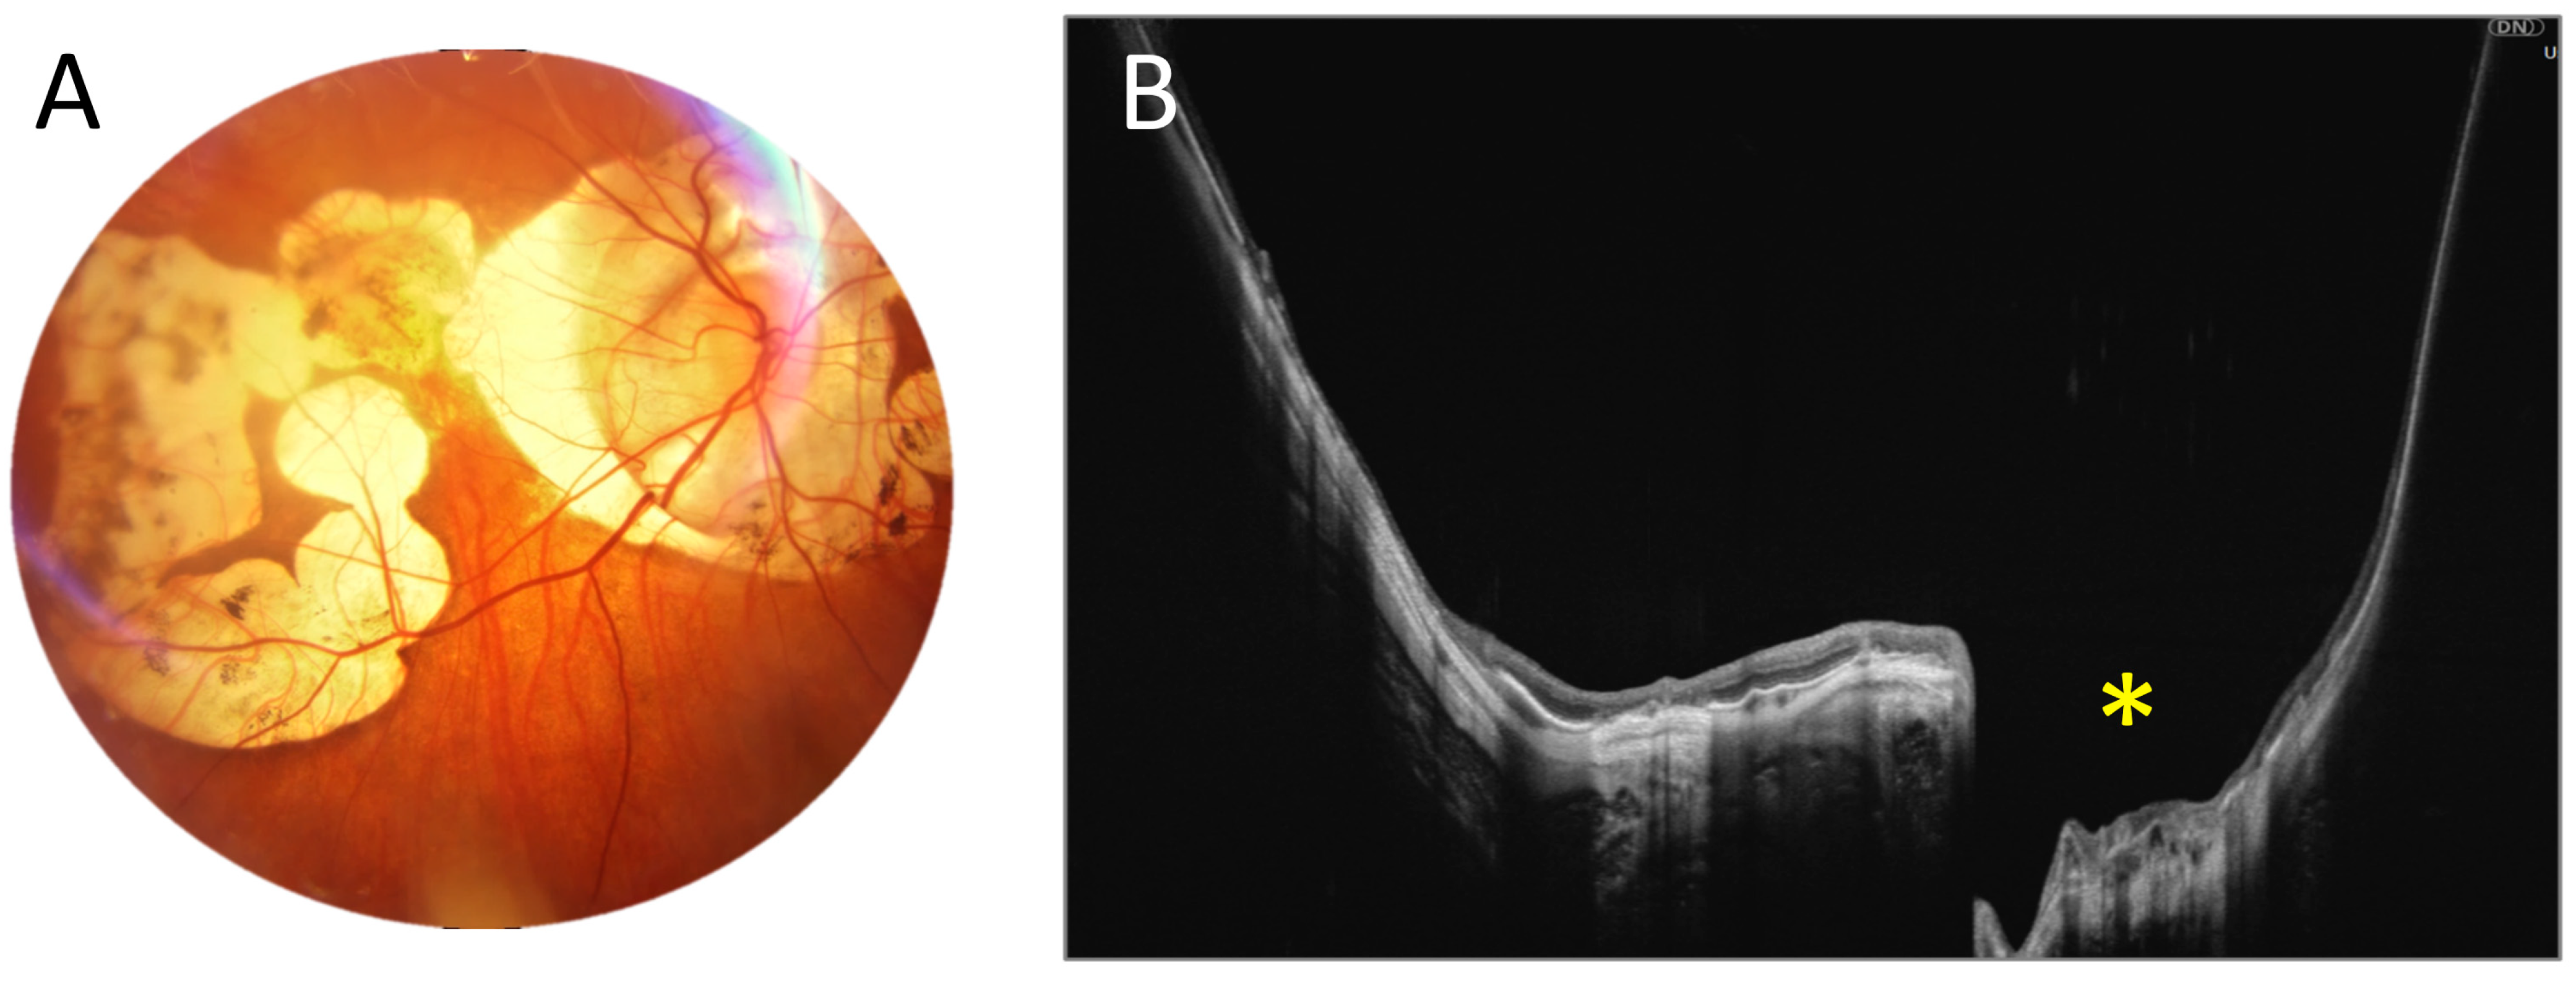

3.1. OCT Measurements

3.3. OCT and Angio-OCT Measurements